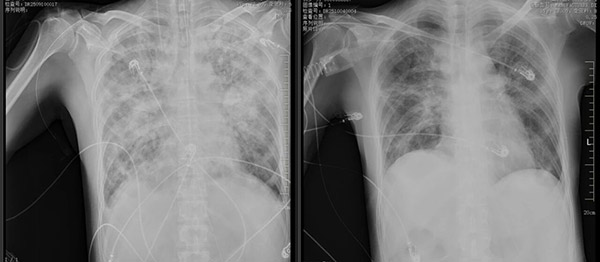

进入ICU后,结合王先生免疫缺陷背景和迅猛的肺部影像学变化,团队迅速将怀疑目标锁定在机会性感染上。经过精准的病原学检测,最终确诊为“耶氏肺孢子菌”感染导致的重症肺炎,并由此引发了急性呼吸窘迫综合征(ARDS)。同时,EB病毒诱发了致命的噬血细胞综合征,使治疗面临严峻挑战。

面对王先生复杂危重的病情,ICU团队沉着应对,多管齐下。呼吸支持方面,以肺保护性通气策略与俯卧位通气为核心,结合每日多次床旁超声评估进行精细化调控;药物治疗上,精准打击耶氏肺孢子菌,有效调节免疫,并辅以全面的营养支持与容量管理;康复团队的早期介入,则为成功脱机拔管提供了重要保障。

在ICU全体医护人员的不懈努力下,王先生的病情终于迎来了转机。肺部病灶逐渐吸收,氧合稳步改善,各项指标趋于正常,10天后成功拔管,20天后完全脱离氧气。转出ICU时,他的脸上绽放着久违的笑容,紧握医护人员的双手哽咽道:“是你们,把我从鬼门关拉了回来。”